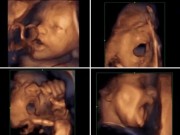

Em bé sinh non ở tuần 23 thai kỳ trong khi người anh em của bé vẫn nằm trong bụng mẹ.

Tuy nhiên, ngay sau khi ca phẫu thuật diễn ra, mẹ Holli Gorveatt đã nhận thấy những cơn đau bụng và bước vào ca sinh nở. Em bé khi đó chào đời chỉ mới 23 tuần với cân nặng 0,5kg và sức khỏe rất yếu. Nhưng điều đáng ngạc nhiên hơn cả là người anh em song sinh cùng bé vẫn nằm trong bụng mẹ và vẫn phát triển bình thường.

Theo các chuyên gia, hiện tại sức khỏe của thai nhi trong bụng mẹ Holli Gorveatt đang phát triển tốt và có thể sẽ chào đời trong khoảng thời gian dự sinh vào đầu năm tới. Điều này đồng nghĩa với việc cặp song sinh này sẽ có hai ngày sinh nhật khác nhau.